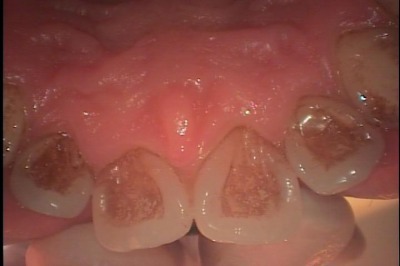

口腔内を見てみますと、一見大きな虫歯は無いように見えますが、

レントゲン写真では左上第二大臼歯の近心に大きな虫歯が確認できます。

- 初診時・口腔内写真

- 初診時・レントゲン写真